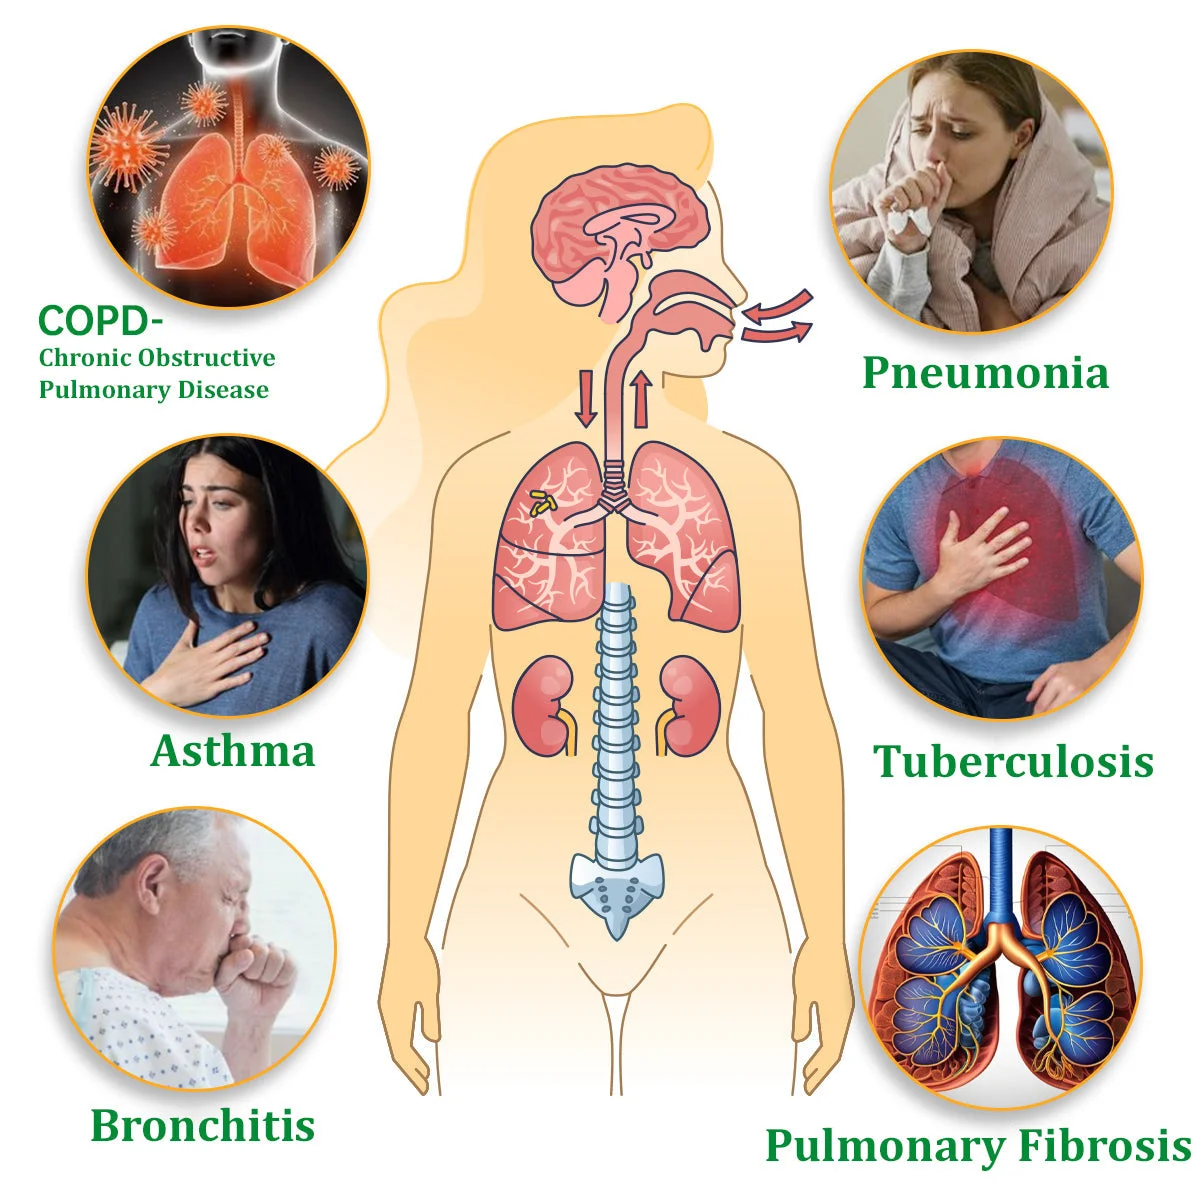

Q3: Can the BQYOOM™ Mullein Diffuser help relieve asthma or bronchitis symptoms?

A: Yes, the BQYOOM™ Mullein Relaxation Stick’s soothing herbal aroma can help relieve symptoms associated with asthma, bronchitis, and other respiratory discomforts by promoting easier breathing and soothing airway irritation.